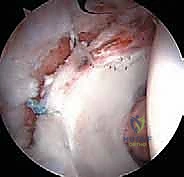

الخطوة 3: الاستكشاف بكاميرا 4K

يتم إدخال منظار مزود بكاميرا عالية الدقة (4K) وإضاءة قوية. تُعرض الصورة مكبرة على شاشة أمام الجراح، مما يسمح له برؤية أدق تفاصيل الغضروف والشفا الحقي بوضوح يفوق الرؤية بالعين المجردة.

الخطوة 4: معالجة الانحشار ونحت العظام (Osteochondroplasty)

باستخدام أدوات دقيقة وصغيرة جداً (مثل المبرد الآلي)، يقوم الدكتور هطيف بإزالة النتوءات العظمية الزائدة.

* إذا كان الانحشار من نوع "الكامة"، يتم نحت عنق عظم الفخذ ليعود لشكله الانسيابي.

* إذا كان من نوع "الكماشة"، يتم تشذيب حافة الحُق الزائدة.

الخطوة 5: إصلاح الشفا الحقي (Labral Repair)

إذا كان الشفا الحقي ممزقاً (وهو أمر شائع جداً)، لا يتم استئصاله، بل يحرص الدكتور هطيف على إصلاحه للحفاظ على وظيفة المفصل. يتم ذلك باستخدام "خطاطيف خياطة" (Suture Anchors) صغيرة جداً تُزرع في العظم وتُستخدم لربط وخياطة الشفا وإعادته لمكانه الطبيعي.